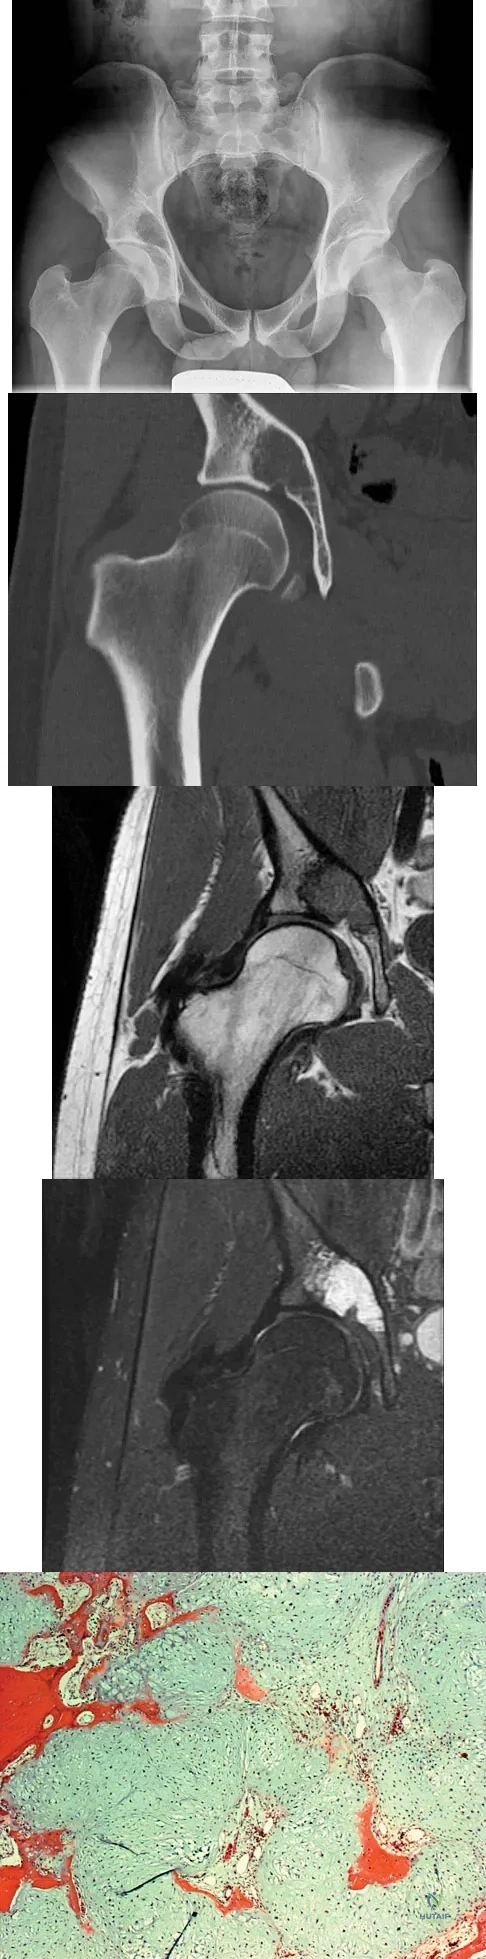

Question 100

A 21-year-old man has had right groin pain for the past year. A radiograph, CT scan, MRI scans, and a biopsy specimen are shown in Figures 50a through 50e. What is the most likely diagnosis?

Explanation